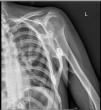

The patient was a 29-year-old woman, with a history of type 1A diabetes and primary amenorrhea secondary to cervical agenesis. At the age of 10 years, she was examined because she had developed a tumor in the cervical region, with no previous injury; she underwent a radiological study and bone biopsy that was compatible with myositis ossificans. Over the years, large ectopic ossifications developed in her shoulders, hips, knees, ankles and paravertebral muscles, which produced a marked secondary thoracolumbar scoliosis and a considerably generalized functional limitation. A plain radiology study of the affected areas showed the existence of exuberant bone bridges at different stages of maturation, that provoked the locking and ankylosing of a number of joints, including a knee (Fig. 1), the spine (Fig. 2) and a shoulder (Fig. 3). The patient was treated with bisphosphonates and calcium supplements with vitamin D for 5 years, while she was also being followed by the rehabilitation service; however, none of these measures was capable of arresting the course of the disease, which led to the physical disability of the patient.